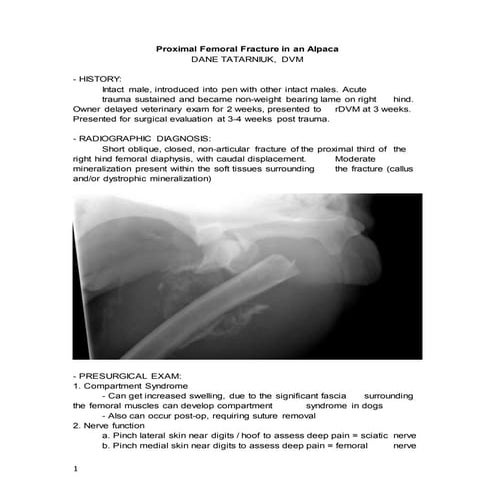

• 5 month, 52kg, male donkey

• Chronic healing SH type 2 fracture of

proximal radius & transverse fracture

of ulna

– 30 degree acquired valgus deformity

• Transverse osteotomy 3cm distal to

original fracture

• Adjustable hinged external ring

fixator

• Applied 1mm distraction per day

• 48 days post-op

– Removed fixator

• 76 days post-op

– Bony callus at osteotomy site

– Correction of valgus deformity